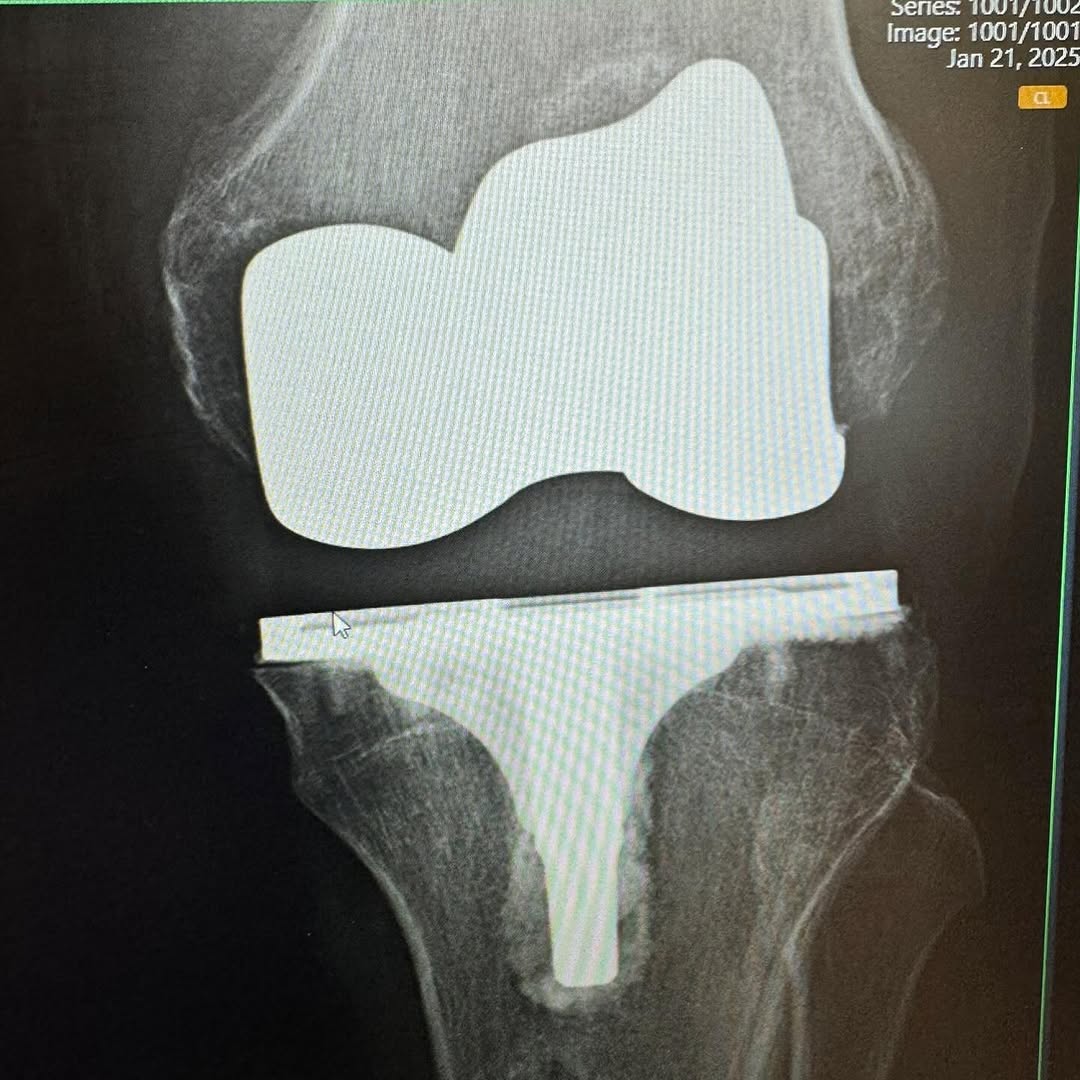

I am 7 weeks post op on a Total Knee Replacement. My left knee was on its last leg, and I have been putting this surgery off for years. Post op X-Rays show everything is healing nicely. Many thanks to Dr. Nicholas Dirig, Derek Bobst, and their excellent team for my surgery. Thanks to Bill Wall of Physical Therapy Specialist for getting me back on track.

Austin shared the following photos: